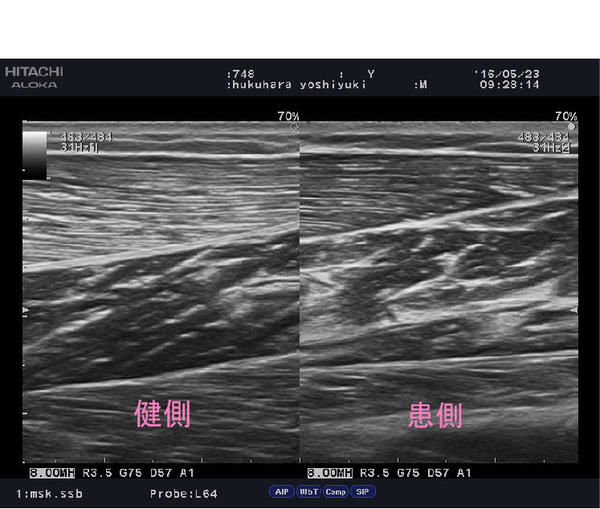

kuff.jpg                                            「ふくらはぎ・ヒラメ筋の炎症」